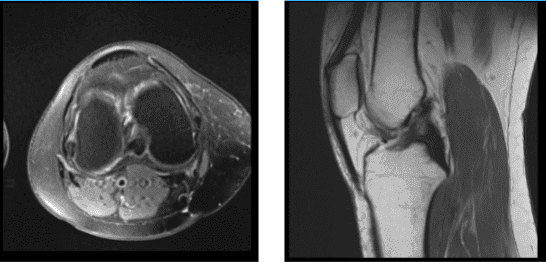

MRI were reviewed and discussed; Collateral Ligaments: The medial collateral ligament is intact. The lateral collateral ligament, biceps femoris tendon, iliotibial band, and popliteus tendon is intact.

Cruciate Ligaments: The anterior and posterior cruciate ligaments are intact. Menisci: Peripheral oblique tear in the body and posterior horn the medial meniscus. The lateral meniscus is intact. Cartilage: The chondral surfaces in the medial compartment are intact. The chondral surfaces in the lateral compartment are intact.

Focal chondral fissure in the medial patellar facet. Bones: The visualized osseous structures demonstrate normal bone marrow and cortical signal intensity without evidence of fracture, trabecular bone injury or dislocation. No osseous lesions are identified.

Extensor Mechanism: The quadriceps and patellar tendons are normal. Joint: Small joint effusion. The soft tissues are otherwise normal. The neurovascular structures demonstrate normal course. It has an impression: Peripheral oblique tear in the body and posterior horn of the medial meniscus. Focal chondral fissure in the medial patella facet. Small joint effusion.

MRI Right Knee Non-contrast